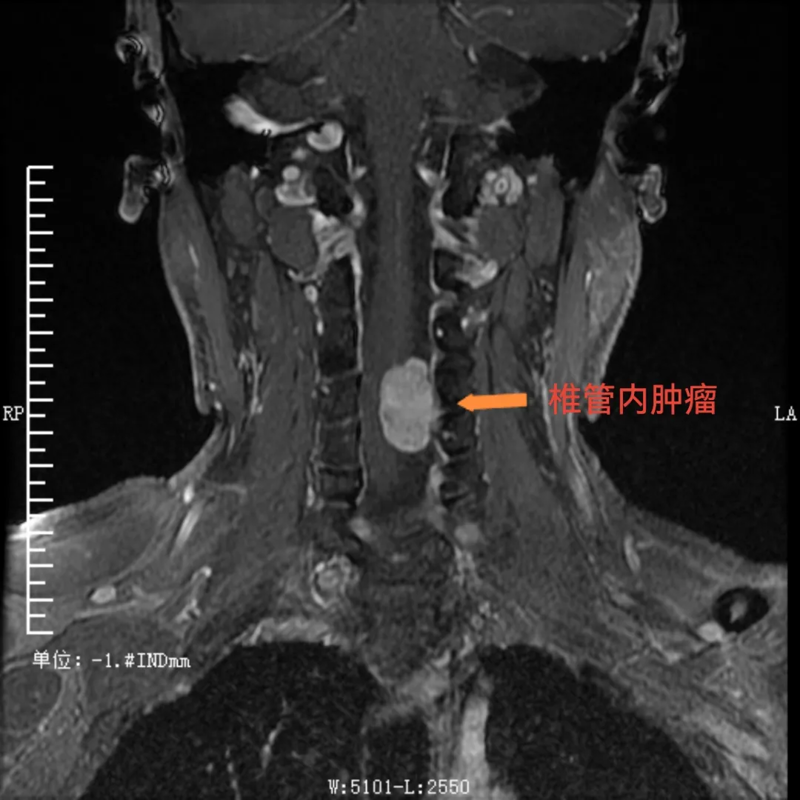

患者潘某(化名),是一位38岁的男性,一直被“左上肢感觉异常、乏力”的症状困扰8个多月。起初,他在贵州荔波县当地医院进行诊治,后根据患者意愿,转到河池市三医院神经外科接受进一步诊疗,到院后,经检查,明确了他的病因:原来是颈椎4-5节段椎管内长了肿瘤。这一肿瘤的存在严重影响了他的神经功能,导致了上肢的不适症状。对于患者来说,这无疑是一个沉重的打击。

术前,可见椎管内肿瘤

面对潘某的病情,河池市三医院的医务人员深知责任重大,立即安抚患者并提供心理疗法,积极为他制定治疗方案。医务部组织神经外科、脊柱外科、麻醉科、重症医学科等院内多学科MDT讨论,仔细研究患者的各项检查结果,不放过任何一个细节。考虑到颈椎部位的手术风险极高,稍有不慎就可能对患者的神经造成不可挽回的损伤。